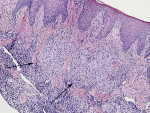

Allergy patch testing, including dental materials was negative. Antineutrophil cytoplasmic antibody level, angiotensin-converting enzyme, and C1 esterase inhibitor were within normal limits. Chest x-ray was unremarkable. An incisional biopsy of maxillary gingival tissue revealed numerous granulomas composed of epithelioid histiocytes admixed with multinucleated giant cells and a diffuse infiltrate of lymphocytes and plasma cells (Figure 3). Periodic acid Schiff, Gomori methanamine silver stain, and acid fast bacilli stain did not reveal any fungal or mycobacterial organisms.